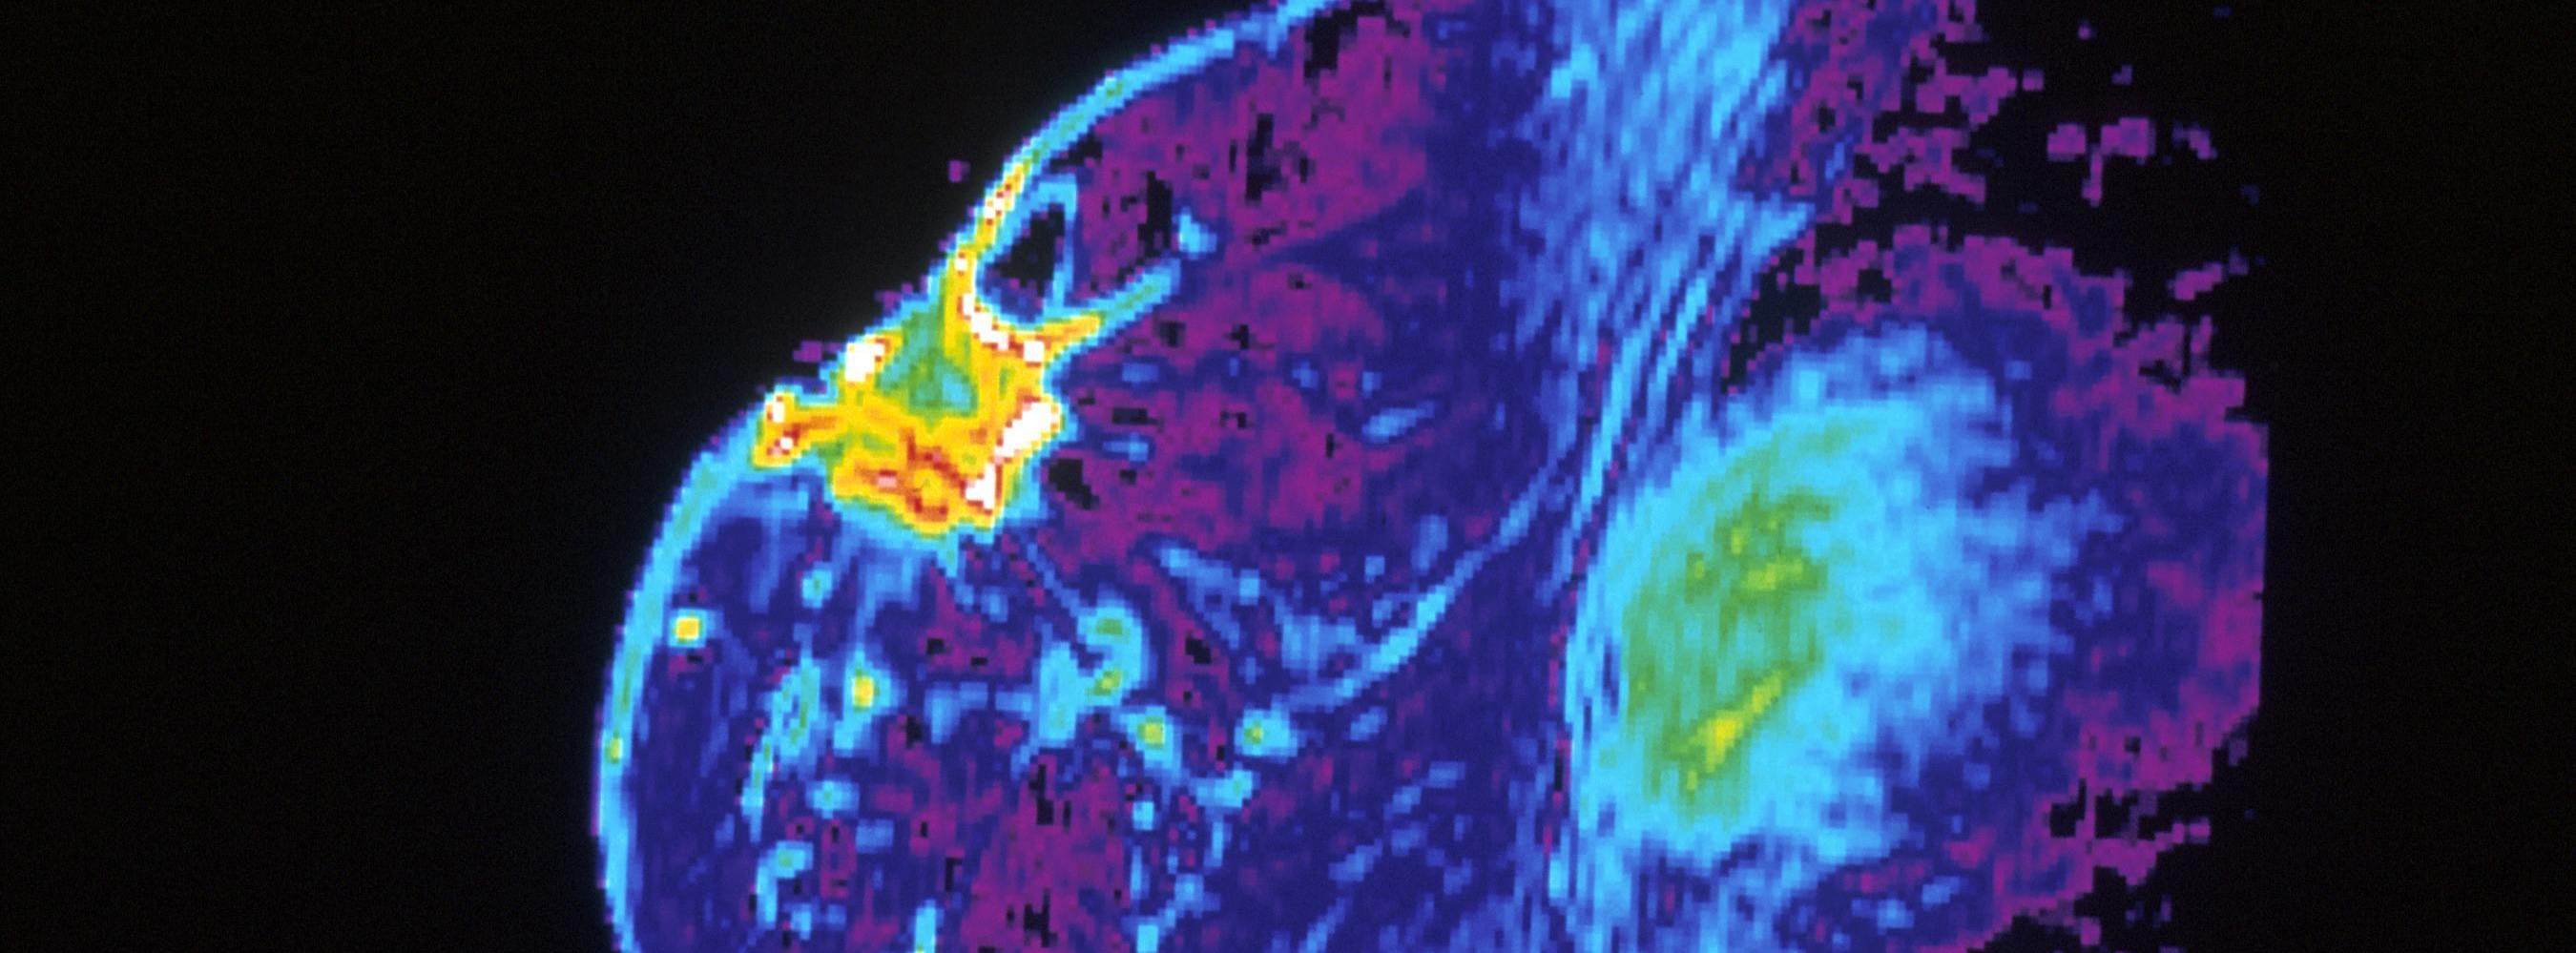

Targeted drug prolongs survival in breast cancer patient group

Patients with HR+ and HER2- node positive high-risk early breast cancer experience improved long term overall survival seven years on, following two years of taking a targeted drug alongside standard hormone therapy, according to new research.